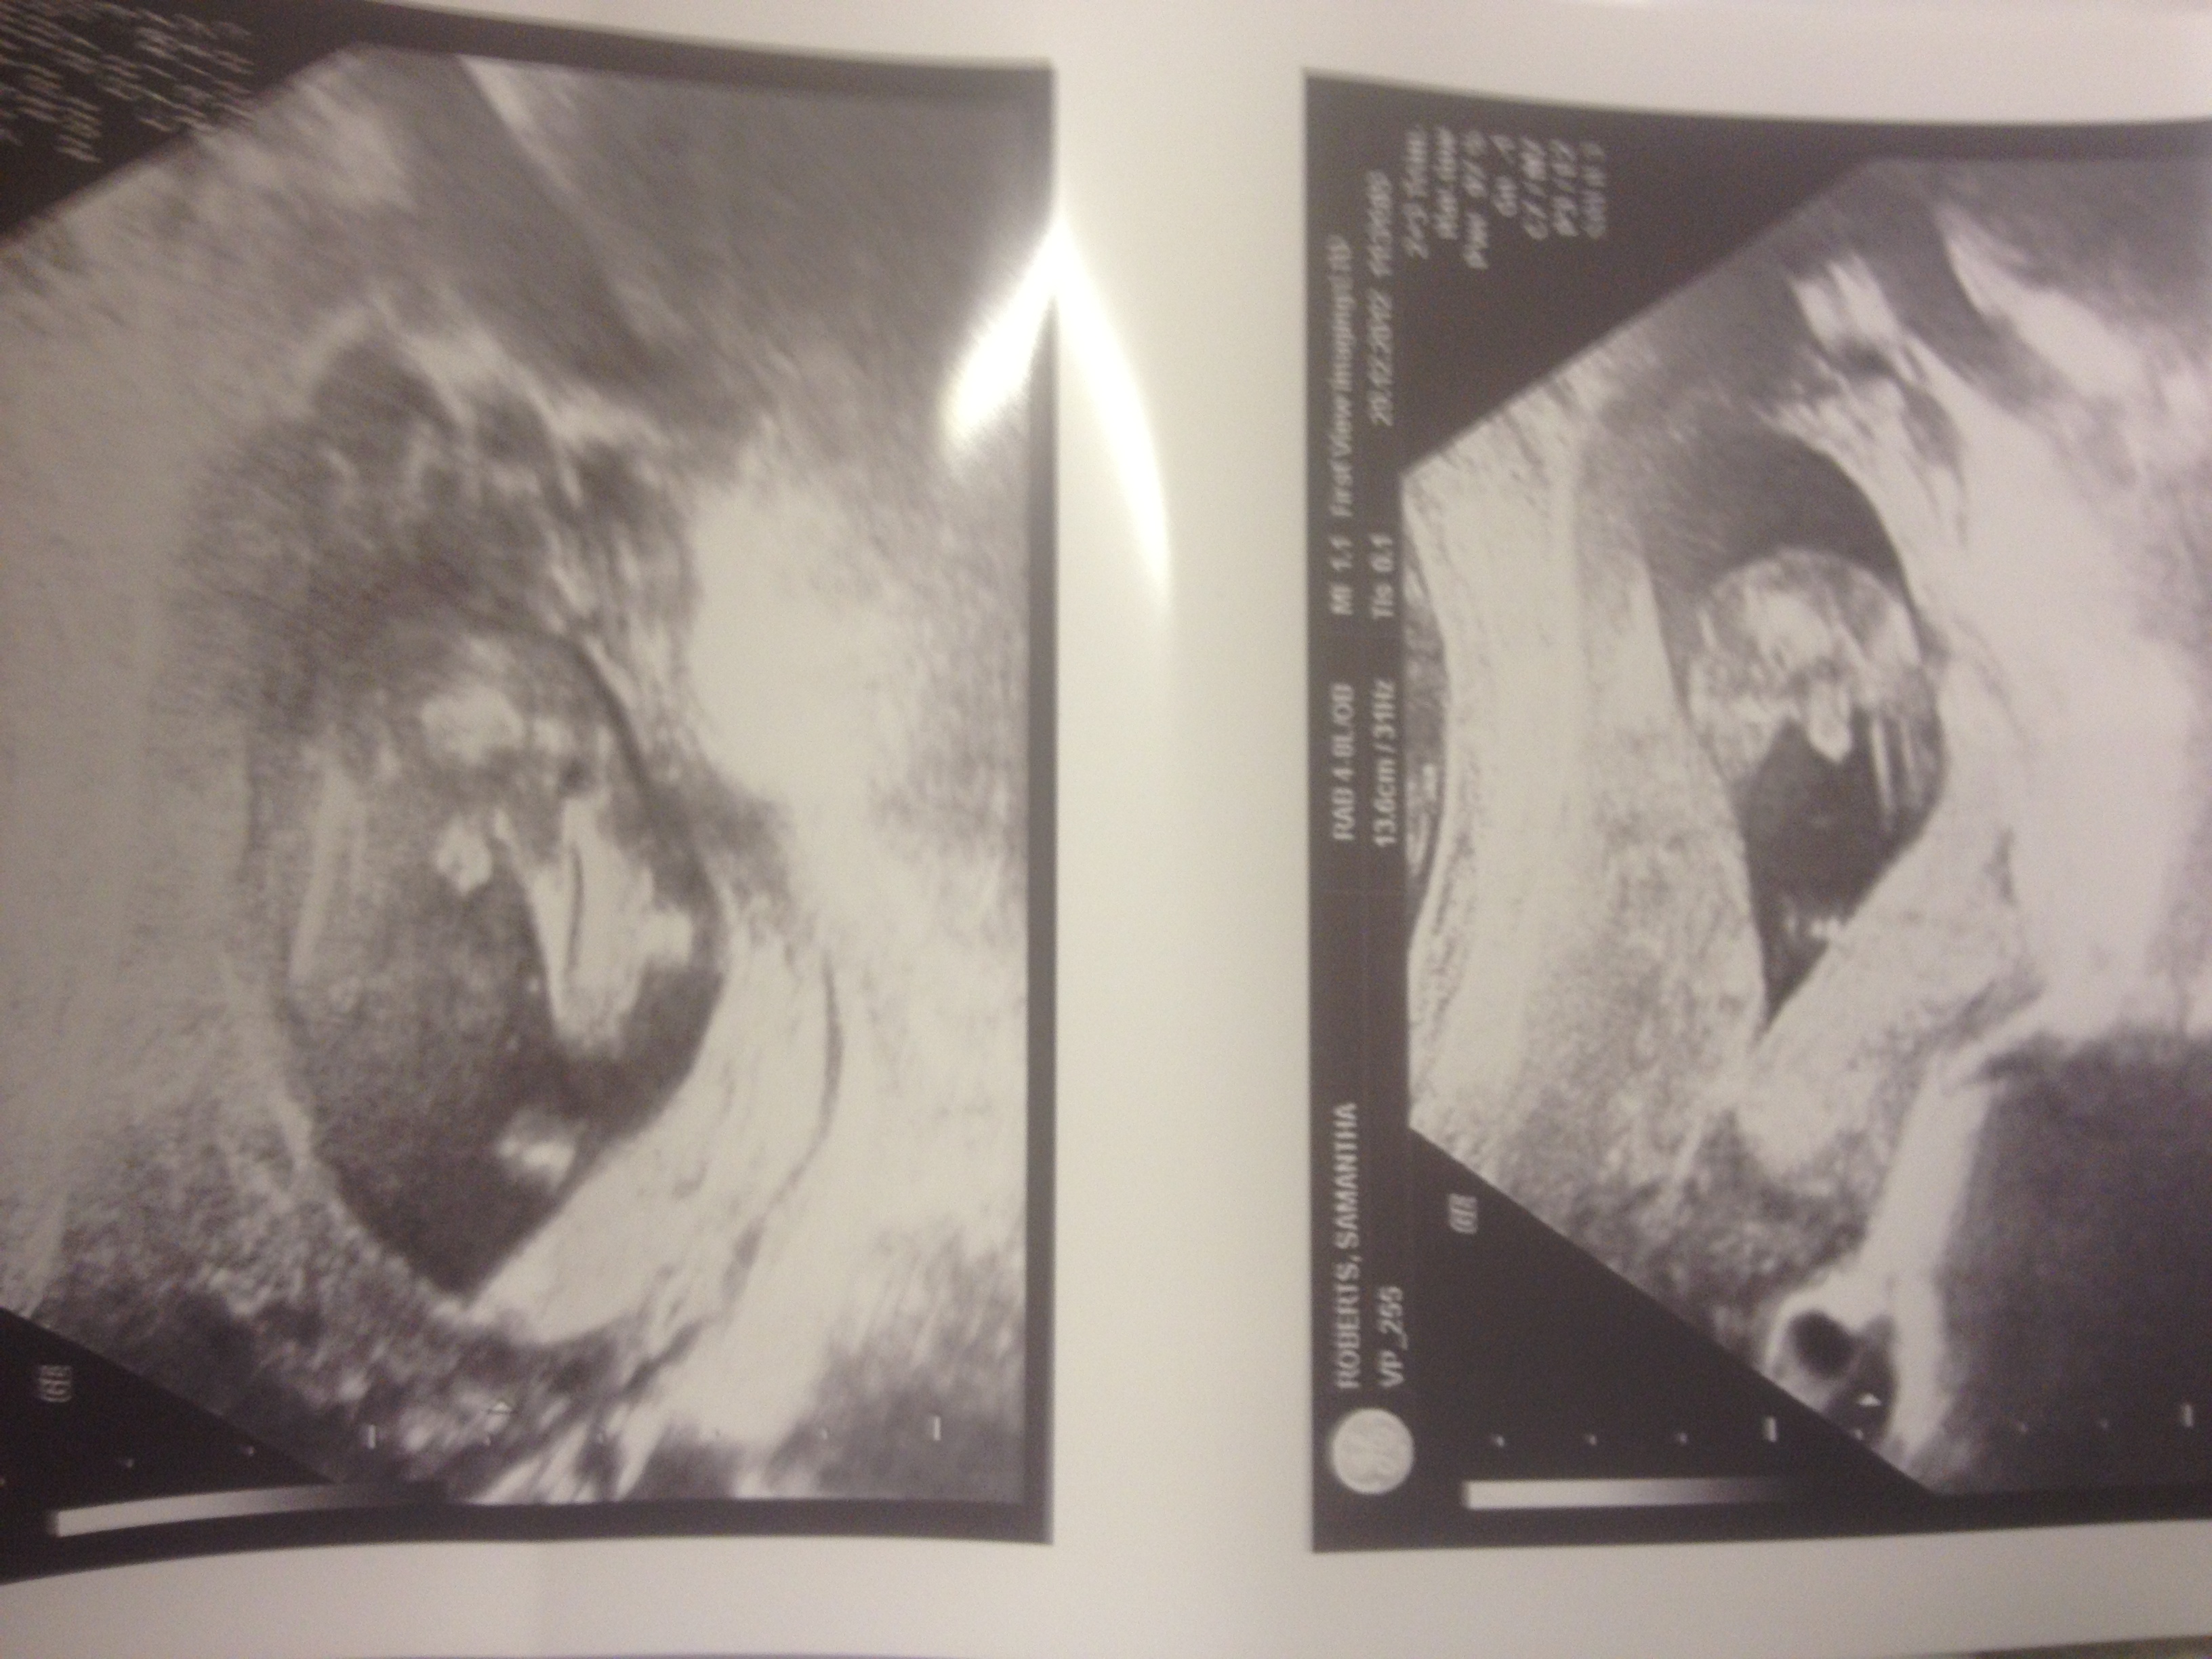

Hi, had a gender scan today at 17 weeks and sonographer was 100% sure it's a boy, do you agree? Mum keeps saying it may be cord as looks so big lol.

Baby Boy for sure, it looks big because the legs are not fully shown in the pic.

Just thought I would post another piccie with both legs full in view.